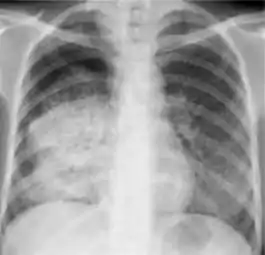

In active pulmonary TB, infiltrates or consolidations and/or cavities are often seen in the upper lungs with or without mediastinal or hilar lymphadenopathy.[1] However, lesions may appear anywhere in the lungs. In HIV and other immunosuppressed persons, any abnormality may indicate TB or the chest X-ray may even appear entirely normal.[1]

Chest X-ray of a person with advanced tuberculosis: Infection in both lungs is marked by white arrow-heads, and the formation of a cavity is marked by black arrows.